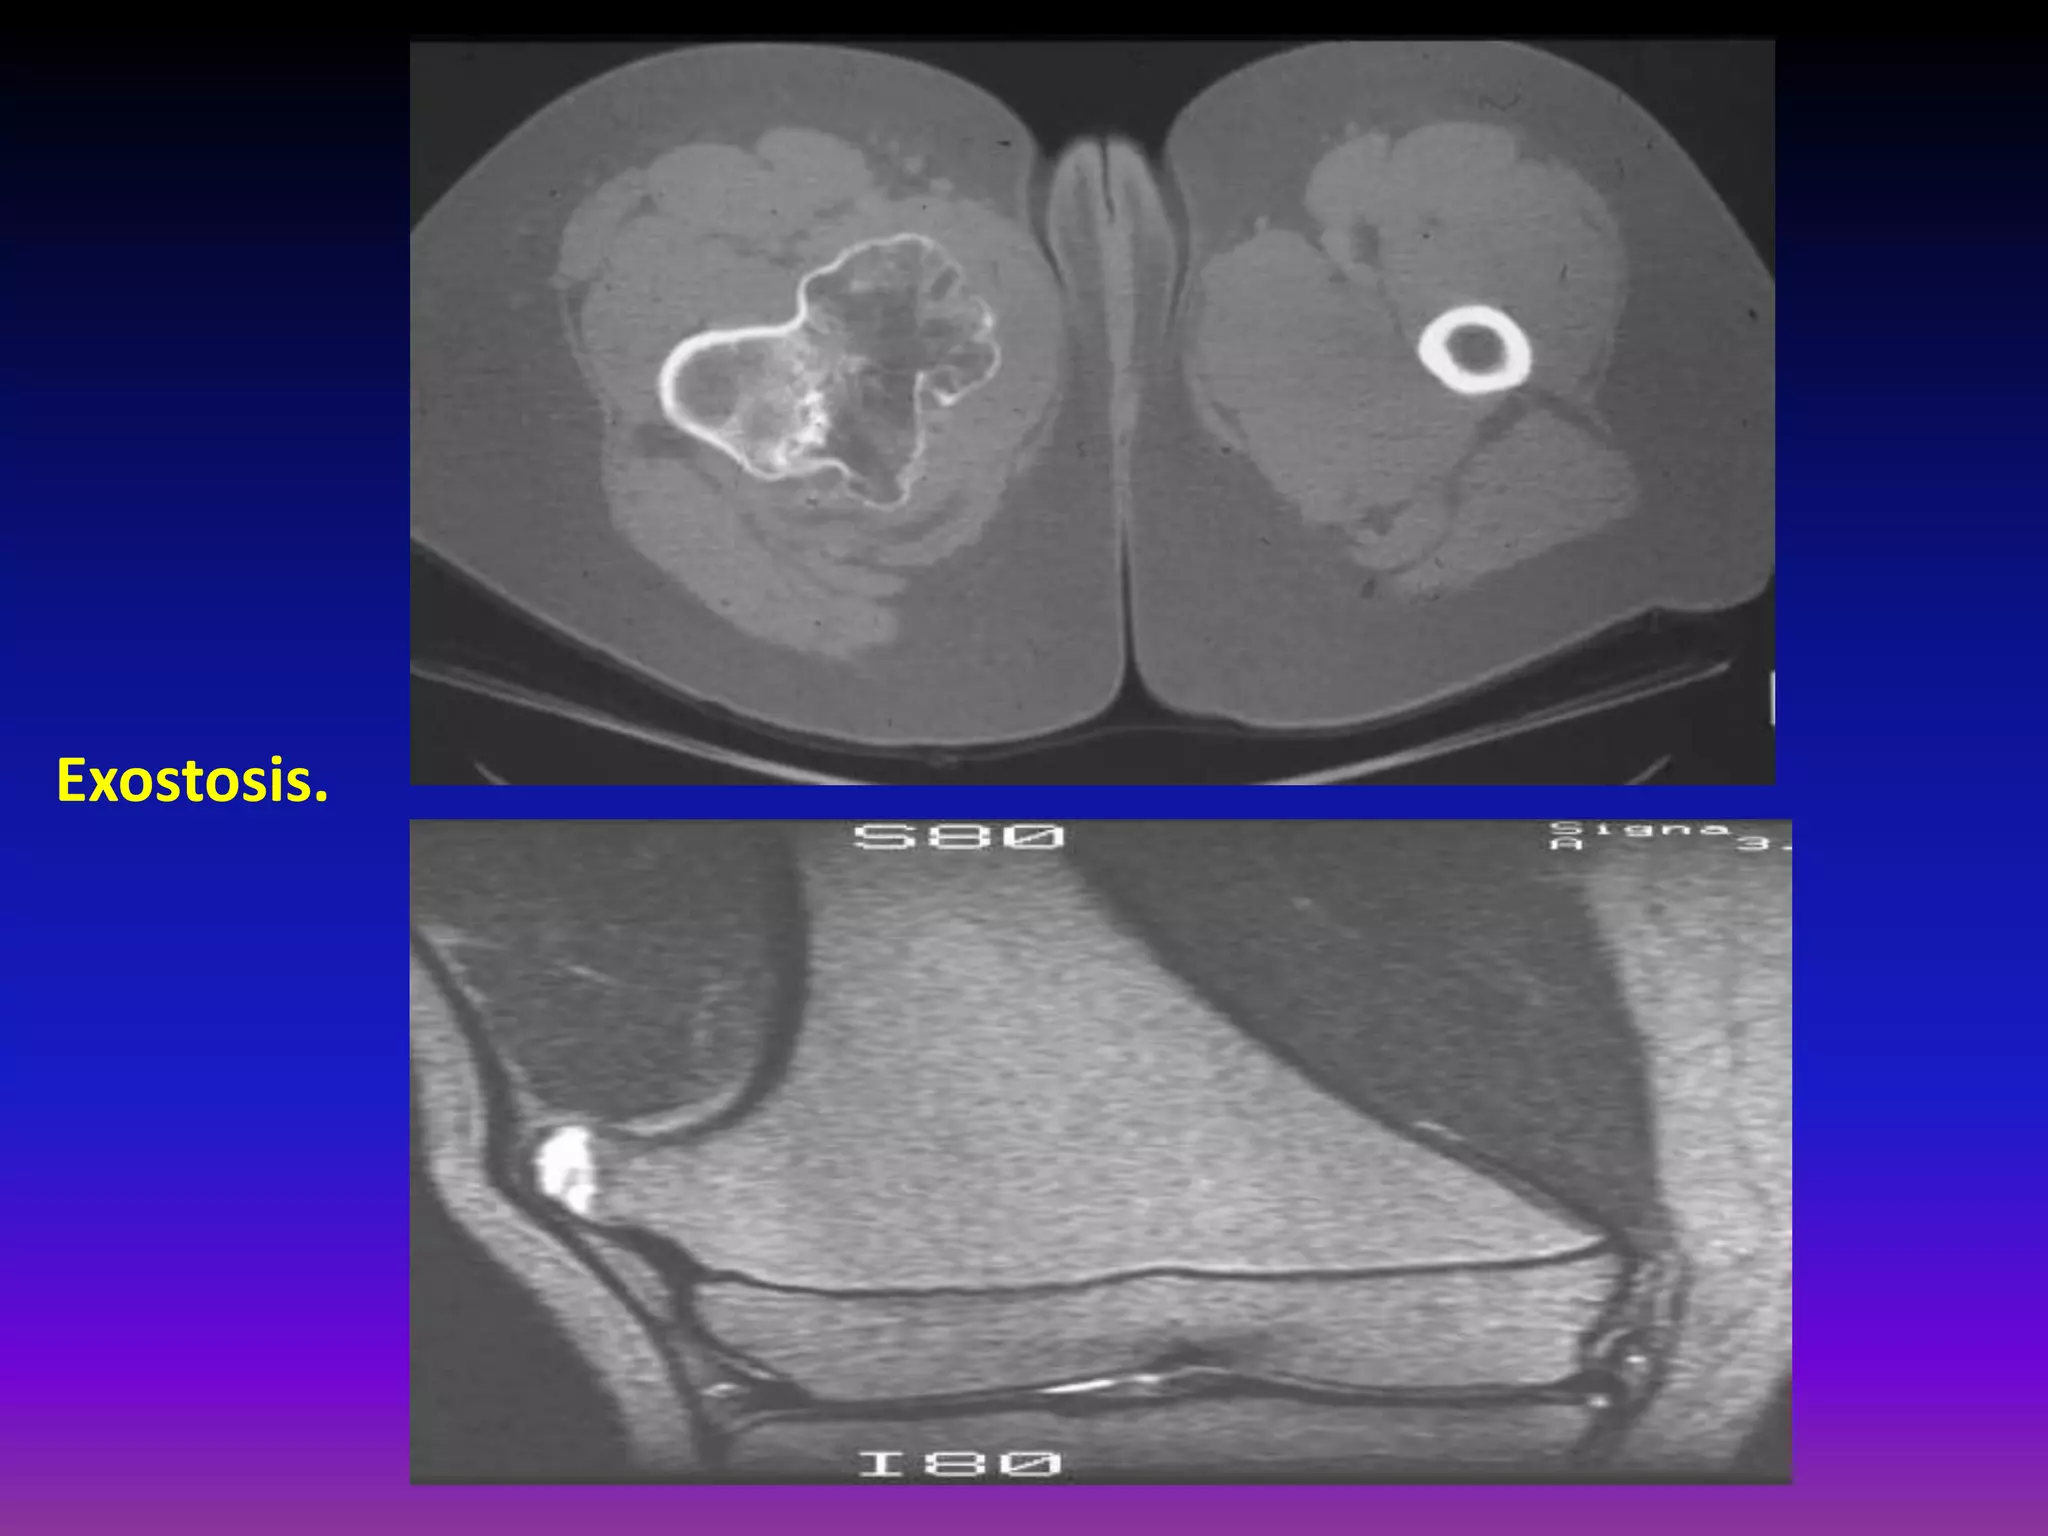

Osteochondroma:

Most common benign skeletal tumor

20-50% of all benign bone tumors.

Most frequent in 1 1st and 2nd decade of life

Male : female = 1.5 : 1.

Most often in juxta -epiphyseal / metaphaseal.

area of long bones (distal femur, proximal tibia)

40% around the knee (also shoulder, hip).

Ostechondroma:

Bony exostosis with cartilage cap.

Typically grow away from physis.

Growth ceases after maturity.

Growth after maturity indicates malignant

transformation.

< 1% risk of malignant transformation for solitary lesions.

Clinical Presentation.

Painless bony mass.

Can be painful if mechanical irritation (nerves, vessels,

muscles, tendons, bones).

Fracture.

Bursa formation.

Radiographic Appearance:

Diagnostic

Sessile or stalk -like

(exostosis).

Metaphyseal bone may be

expanded and remodeled.

Cartilage cap may be calcified.

Base of lesion contiguous

with cortex of bone.

Exostosis.